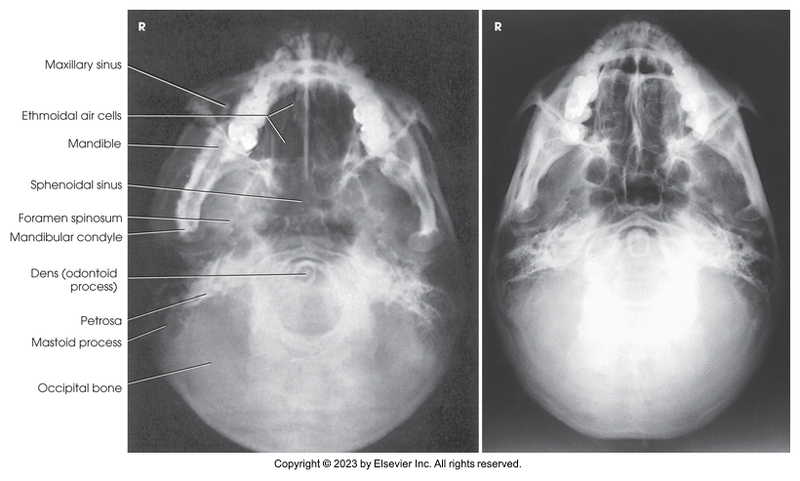

Submentovertical of the cranial base - Schuller method

Submentovertical of cranial base - Schuller method